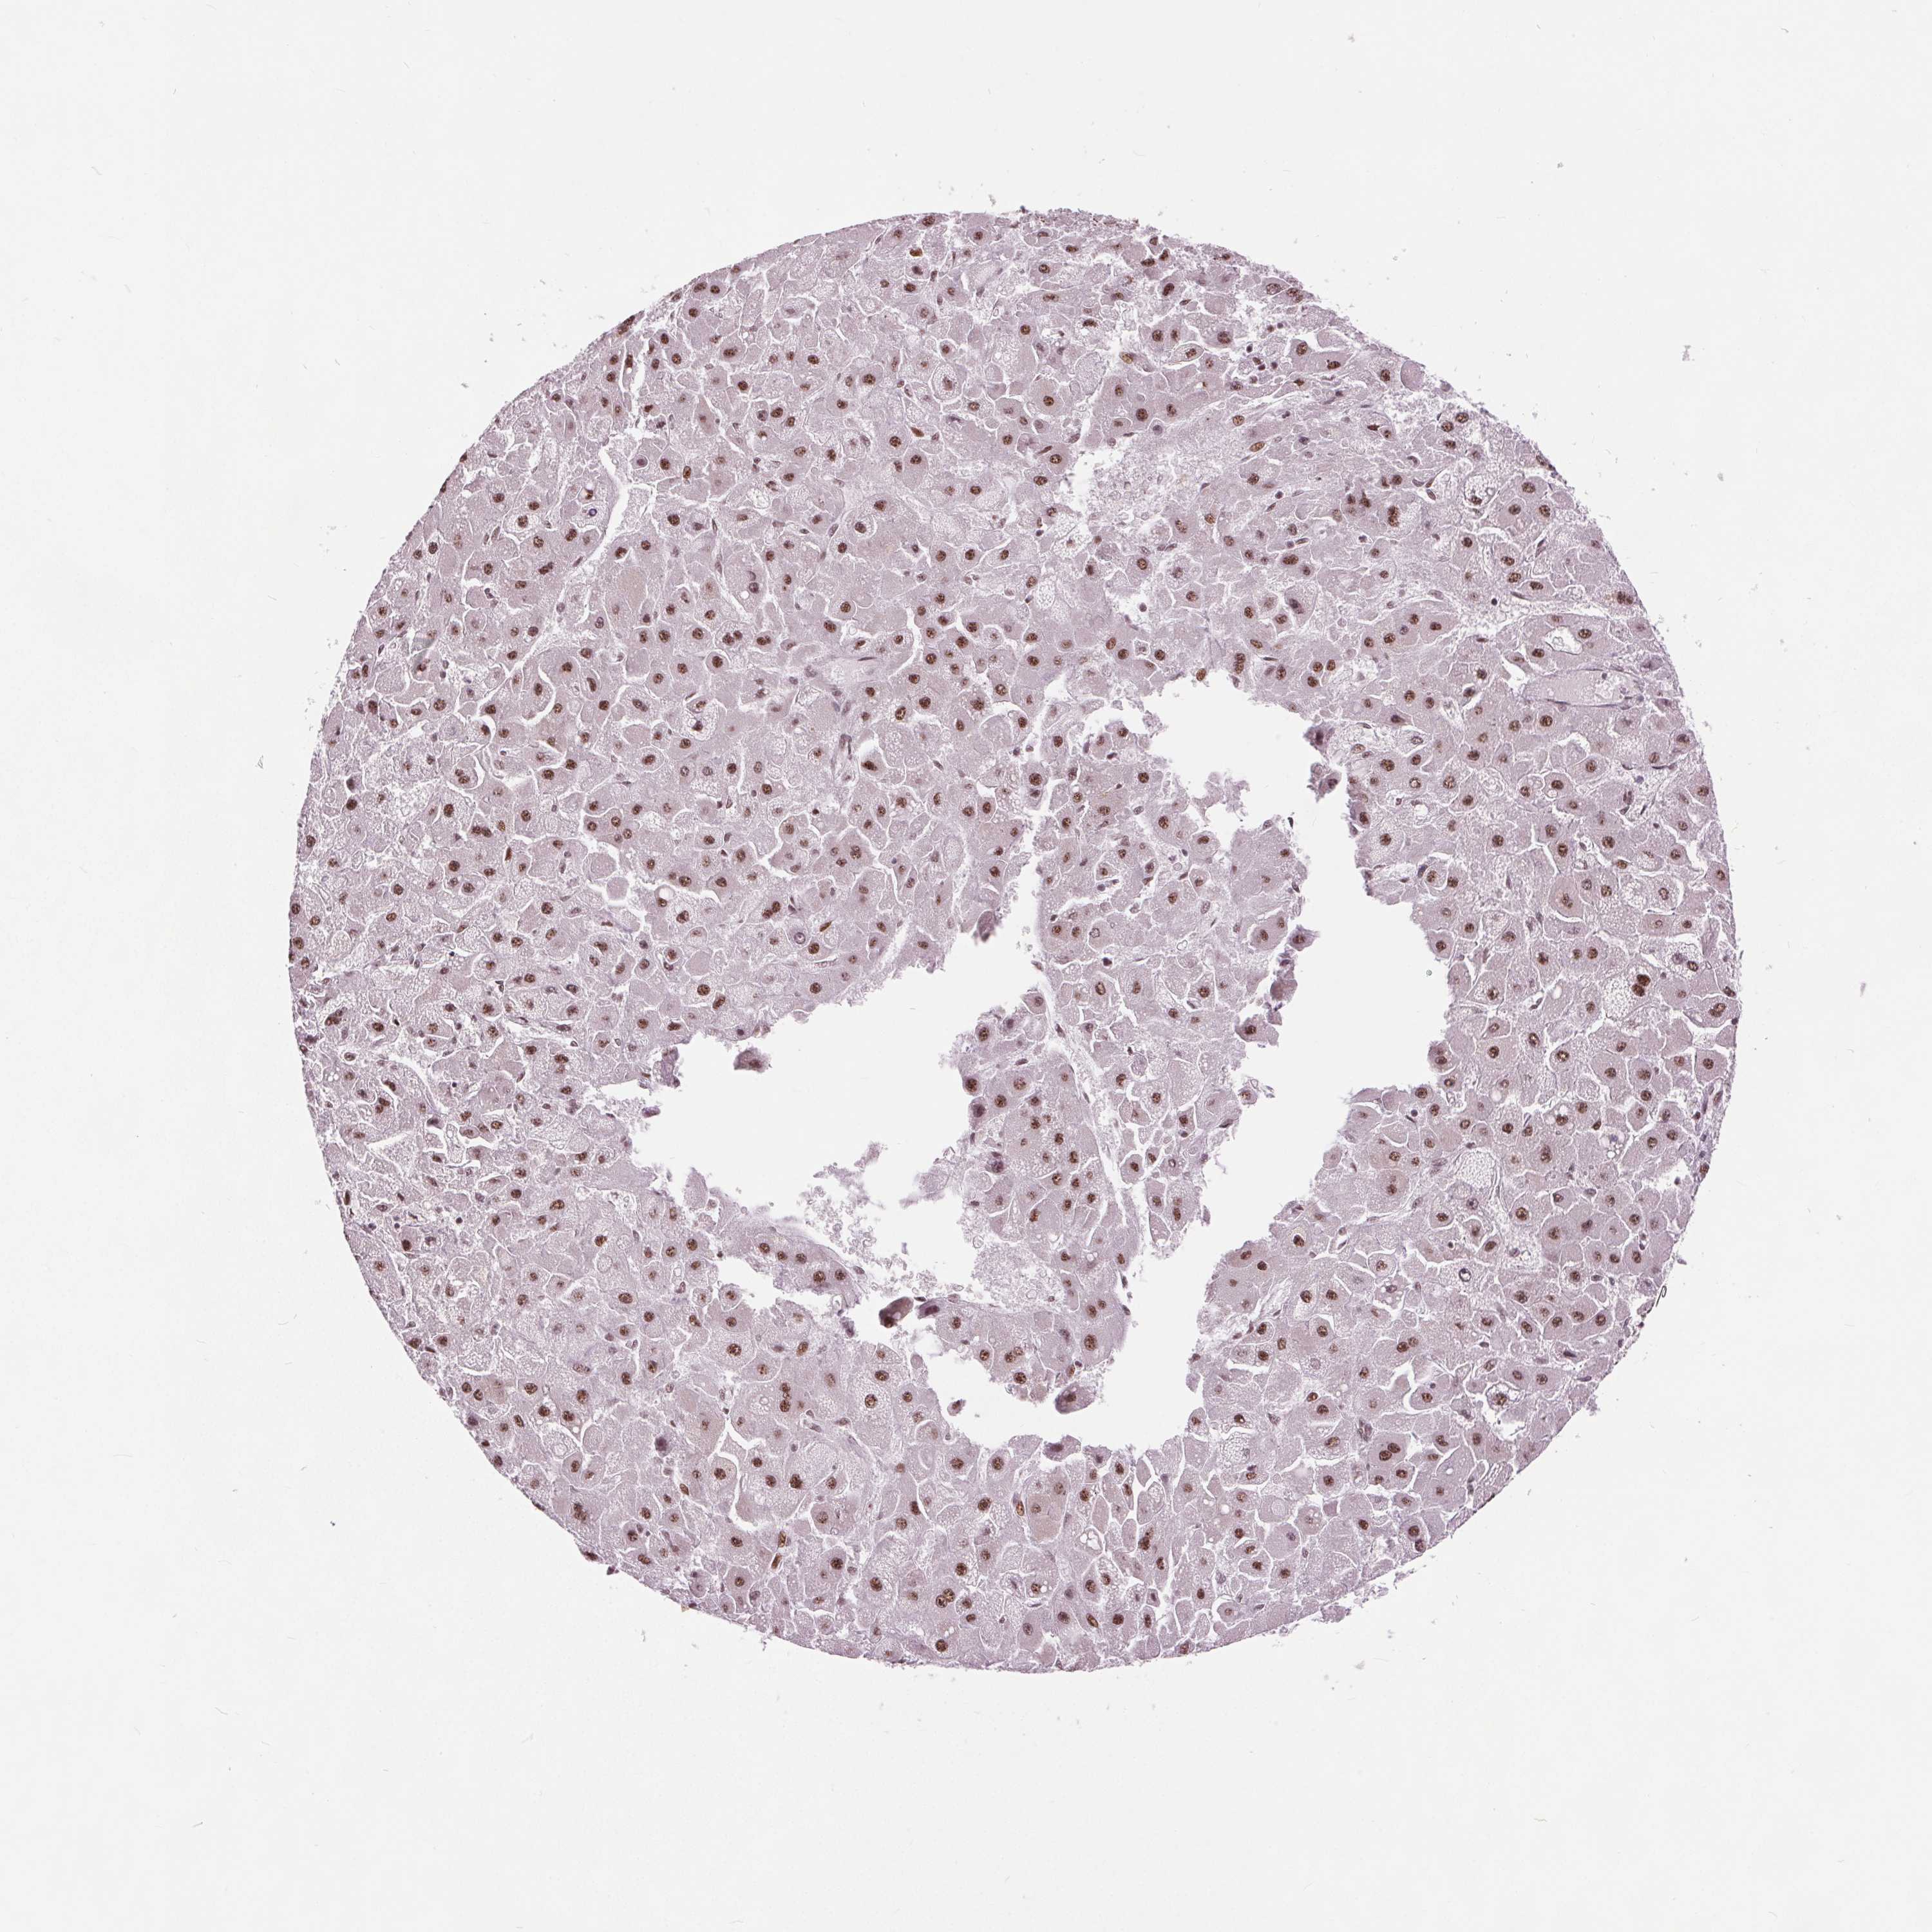

LIVER CANCER - Protein expressioni

A mouse-over function shows sample information and annotation data. Click on an image to view it in a full screen mode. Samples can be filtered based on level of antibody staining by selecting one or several of the following categories: high, medium, low and not detected. The assay and annotation is described here.

Note that samples used for immunohistochemistry by the Human Protein Atlas do not correspond to samples in the TCGA dataset.

Antibody stainingi

Antibody staining in the annotated cell types in the current human tissue is reported as not detected, low, medium, or high, based on conventional immunohistochemistry profiling in selected tissues. This score is based on the combination of the staining intensity and fraction of stained cells.

Each image is clickable and will lead to virtual microscopy that enables deeper exploration of all samples and also displays staining intensity scores, fraction scores and subcellular localization as well as patient and tissue information for each sample.

Antibody HPA066832

Staining

High

Medium

Low

Not detected

Intensity

Strong

Moderate

Weak

Negative

Quantity

>75%

75%-25%

<25%

None

Location

Nuclear

Cytoplasmic/membranous

Cytoplasmic/membranous,nuclear

Carcinoma, Hepatocellular, NOS